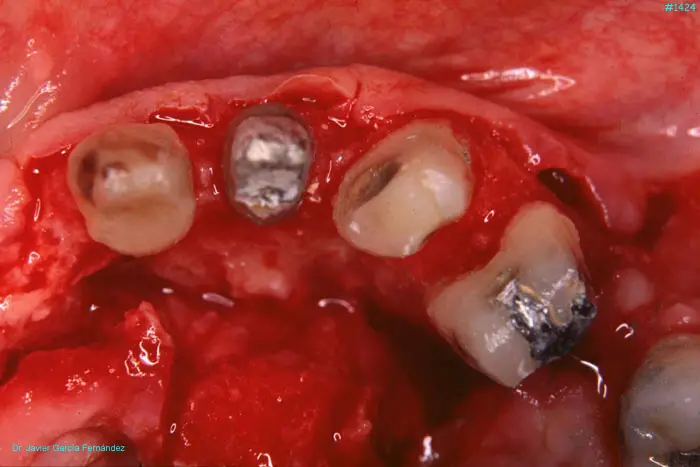

Atlas of Surgical Techniques in Periodontics. Chapter III. Atlas de Técnicas Quirúrgicas en Periodoncia